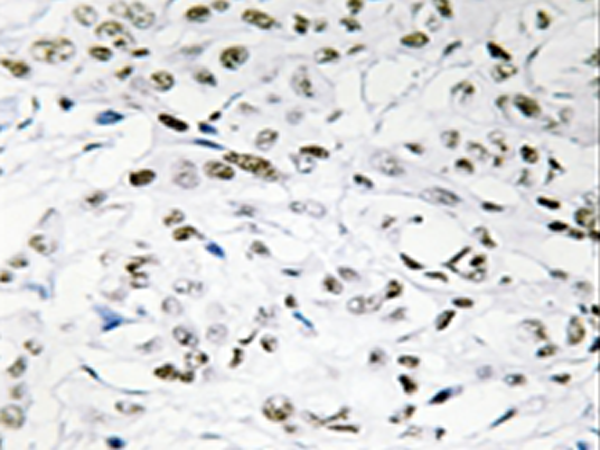

IHC positive control:

Human breast carcinoma tissue

IHC Recommend dilution:

50-100